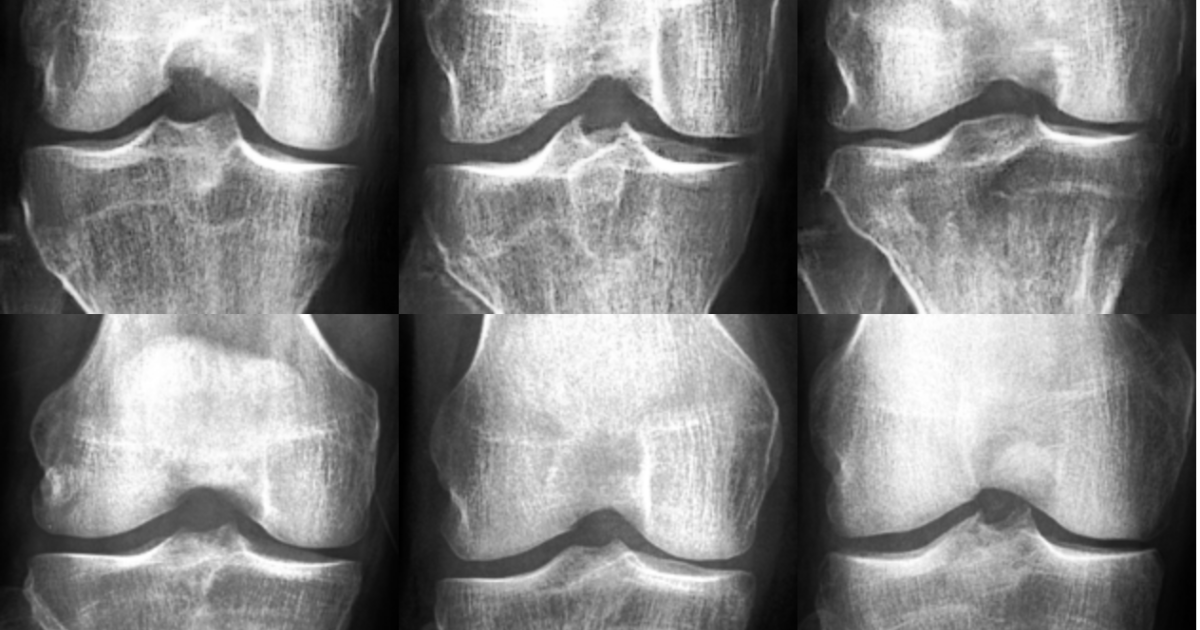

Oheisessa kuvasarjassa on esimerkki synteettisten röntgenkuvien muokkaamisesta. Kuvasarjassa on kuusi animaatiosta otettua kuvankaappausta.

Erikoislääkäreitä pyydettiin ensin tekemään nivelrikkoluokitus kuville ilman että he tiesivät aineiston sisältävän synteettisiä kuvia. Tämän jälkeen toisessa vaiheessa heitä pyydettiin erottelemaan kuvat aitoihin ja synteettisiin kuviin. Testien perusteella synteettisten kuvien havaitseminen aitojen joukosta on erittäin hankalaa jopa asiantuntijalle.

– Täydentämällä aidoista röntgenkuvista koostuvaa dataa synteettisillä kuvilla onnistuimme parantamaan tekoälypohjaisen nivelrikkoluokittimen tarkkuutta, kertoo neuroverkon suunnittelusta vastannut väitöskirjatutkija Fabi Prezja.